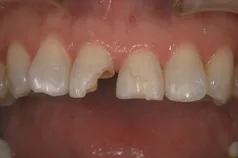

[症例4]

症例3と同様にジルコニア・ブリッジで治療した症例です。

右上中切歯(向かって左上の前歯)が欠損しており、保険のブリッジが入っていました。保険のブリッジは白い部分がレジンという材料でできていますが、経年的に変色するのが大きな欠点です。

治療前は変色があり、歯の長さも不揃いです。

歯の長さがそろうように、歯茎の手術を行い、歯肉がきれいなったあとでジルコニア・ブリッジを装着しています。治療前と比べ、自然で美しい歯になりました。

- 治療期間:6ヶ月

- 治療費:40万円

- 治療回数:18回